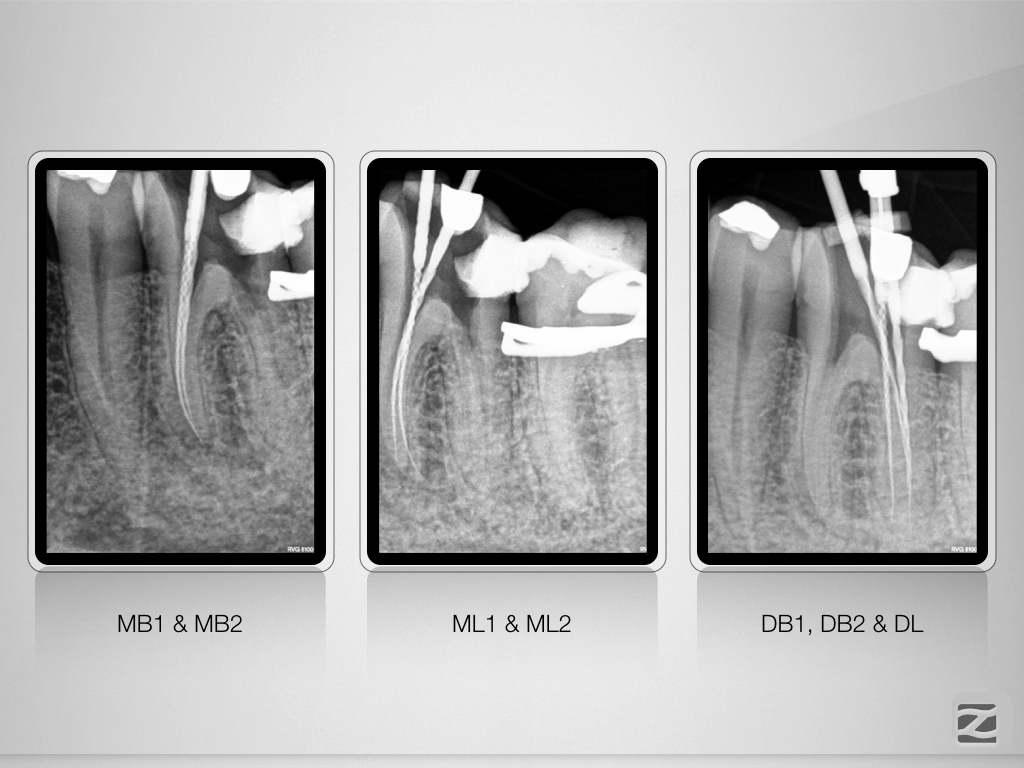

36D.003

7 auf einen Streich